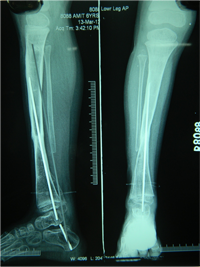

Also known as congenital "Anterolateral Bowing of Tibia" or CPT is a rare condition seen in infants and children. The tibia is bowed and the apex of the deformity in anterior and lateral in the sagittal and coronal plane respectively. Incidence is 1: 140,000. This type of bowing is pathognomomic of CPT or Congenital Pseudarthrosis of tibia, leading to a recalcitrant non-union of the tiba and fibula. Almost 50% of cases are associated with Neurofibromatosis type I or fibrous dysplasia. The deformity may be present at birth or occurs as a painless stress fracture when child starts to walk. The typical site of deformity is in the lower third of the leg and both tibia and fibula may be involved. Radiographs reveal typical bowing and the tibia may have sclerotic edges, cortical tapering, cyst formation and sometimes obliteration of meduallary cavity. CPT that Require Treatment

Rush Rodding Periosteal Grafting

Newer Fassier - Duval rod in an older child. About CPTCPT is a disorder of the tibia where there is a propensity for recurrent fractures, poor healing of bone and need for multiple operations. Current methods of treatment of CPT have evolved to give much more consistent results than previously possible. Special methods are available to achieve union. |